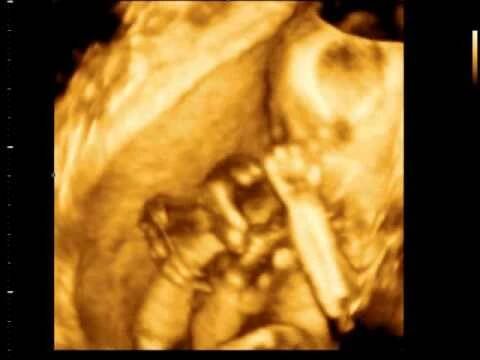

3D ultrazvuk 23.týden

Jaký je rozdíl mezi 3D a 4D ultrazvukem?Snímek 3D je dokonale plastická fotografie vašeho miminka, zcela reálná v daném čase a prostoru. V případě 4D zobrazení jde technický pokrok ještě dále a vy máte díky této technologii možnost vidět i reálný pohyb miminka natočený na videozáznam.

Kdy se tento ultrazvuk provádí?Za ideální čas pro 3D a 4D snímek je považované období od 24. do 28. týdne těhotenství. Každé středisko ale uvádí jiné týdny, obvykle však v rozptylu od 20. do 31. týdne.